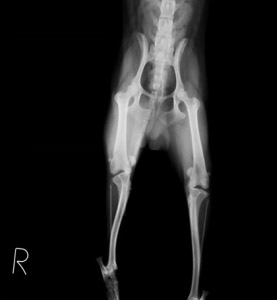

主訴:半年前からたびたび右後足を挙上していましたが、2週前から全く足をつけなくなったとのことで来院されました。レントゲン検査にて右は完全に膝蓋骨が内方に脱臼しており、左側も膝蓋骨内方脱臼が認められたため、両側とも整復手術を行いました。

術前レントゲン:

両側とも膝蓋骨が内方脱臼しており、特に右側が重度でした。 -